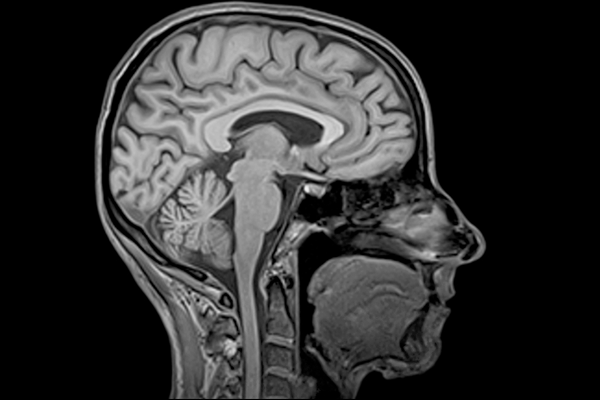

Магнитно-резонансная томография считается наиболее чувствительным способом обследование разных органов человека, включая головной мозг и нервную систему. Полученные при обследовании снимки требуют профессиональной расшифровки. Сервис дистанционной расшифровки снимков online-mrt.ru.

Результаты МРТ подтвердить или исключить возможность заболевания данного органа, в момент его начального развития. Полученный снимок выглядит как темный лист, на котором изображены непонятные для обычного человека вещи, в разных плоскостях.

Создаваемые прибором картинки включают более темные и светлые участки. Использование разной контрастности в одном и том же снимке позволяет рассмотреть орган детально.

МРТ позволяет проводить эффективную диагностику большого числа заболеваний, включая проблемы связанные с головным мозгом, позвоночником, кроветворительной системой и другими органами. Информативность его проведения достаточно высокая. Но оценка полученных результатов требует специальной подготовки. Занимаются расшифровкой специалисты-рентгенологи. Поэтому результата не выдают на руки сразу. Для создания описания требуется определенное время.